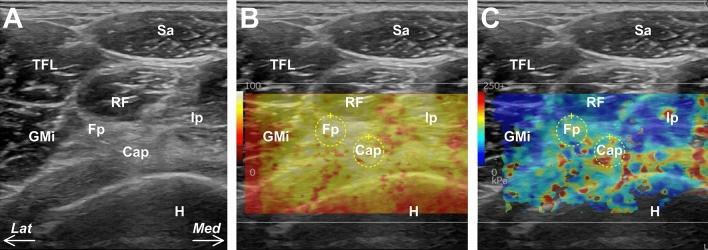

Recently, pathological changes in the fat pad on the anterior inferior iliac spine (AIIS), between the proximal rectus femoris and joint capsule, have been highlighted as a cause of anterior hip pain. However, precise fat pad features, such as the spatial distribution distal to the AIIS, histological features, and in vivo tissue elasticity, remain unclear. This study aimed to investigate the morphological characteristics of the fat pad on the AIIS. Four hips from four cadaveric donors were both macroscopically and histologically investigated, and eight hips from four volunteers were assessed using ultrasonography. The fat pad on the AIIS was also surrounded by the iliopsoas and gluteus minimus, extending distally to the superficial portion of the vastus lateralis, and the anterior portion of the gluteus maximus tendon. Histological analysis revealed that the fat pad was composed of loose connective tissue. Based on the ultrasonography, the shear wave velocity in the fat pad was significantly lower than that in the joint capsule. Conclusively, the pathological adhesion between the joint capsule and pericapsular muscles, if caused by fat pad fibrosis, may occur following the abovementioned fat pad spatial distribution.

最近,人们强调了髂前下棘(AIIS)前脂肪垫(位于近端股直肌和关节囊之间)的病理学变化是导致髋关节前侧疼痛的原因之一。然而,脂肪垫的精确特征,如在 AIIS 远端的空间分布、组织学特征和体内组织弹性,仍不清楚。本研究旨在探讨 AIIS 处脂肪垫的形态特征。从四个尸体供体的四个髋关节进行了宏观和组织学研究,并对四个志愿者的八个髋关节进行了超声检查。AIIS 处的脂肪垫被髂腰肌和小臀肌包围,向股外侧肌浅部和臀大肌肌腱前部分延伸。组织学分析显示,脂肪垫由疏松结缔组织组成。根据超声检查,脂肪垫的剪切波速度明显低于关节囊。综上所述,如果关节囊和关节囊周围肌肉的病理性粘连是由脂肪垫纤维化引起的,那么这种粘连可能会沿着上述脂肪垫的空间分布发生。